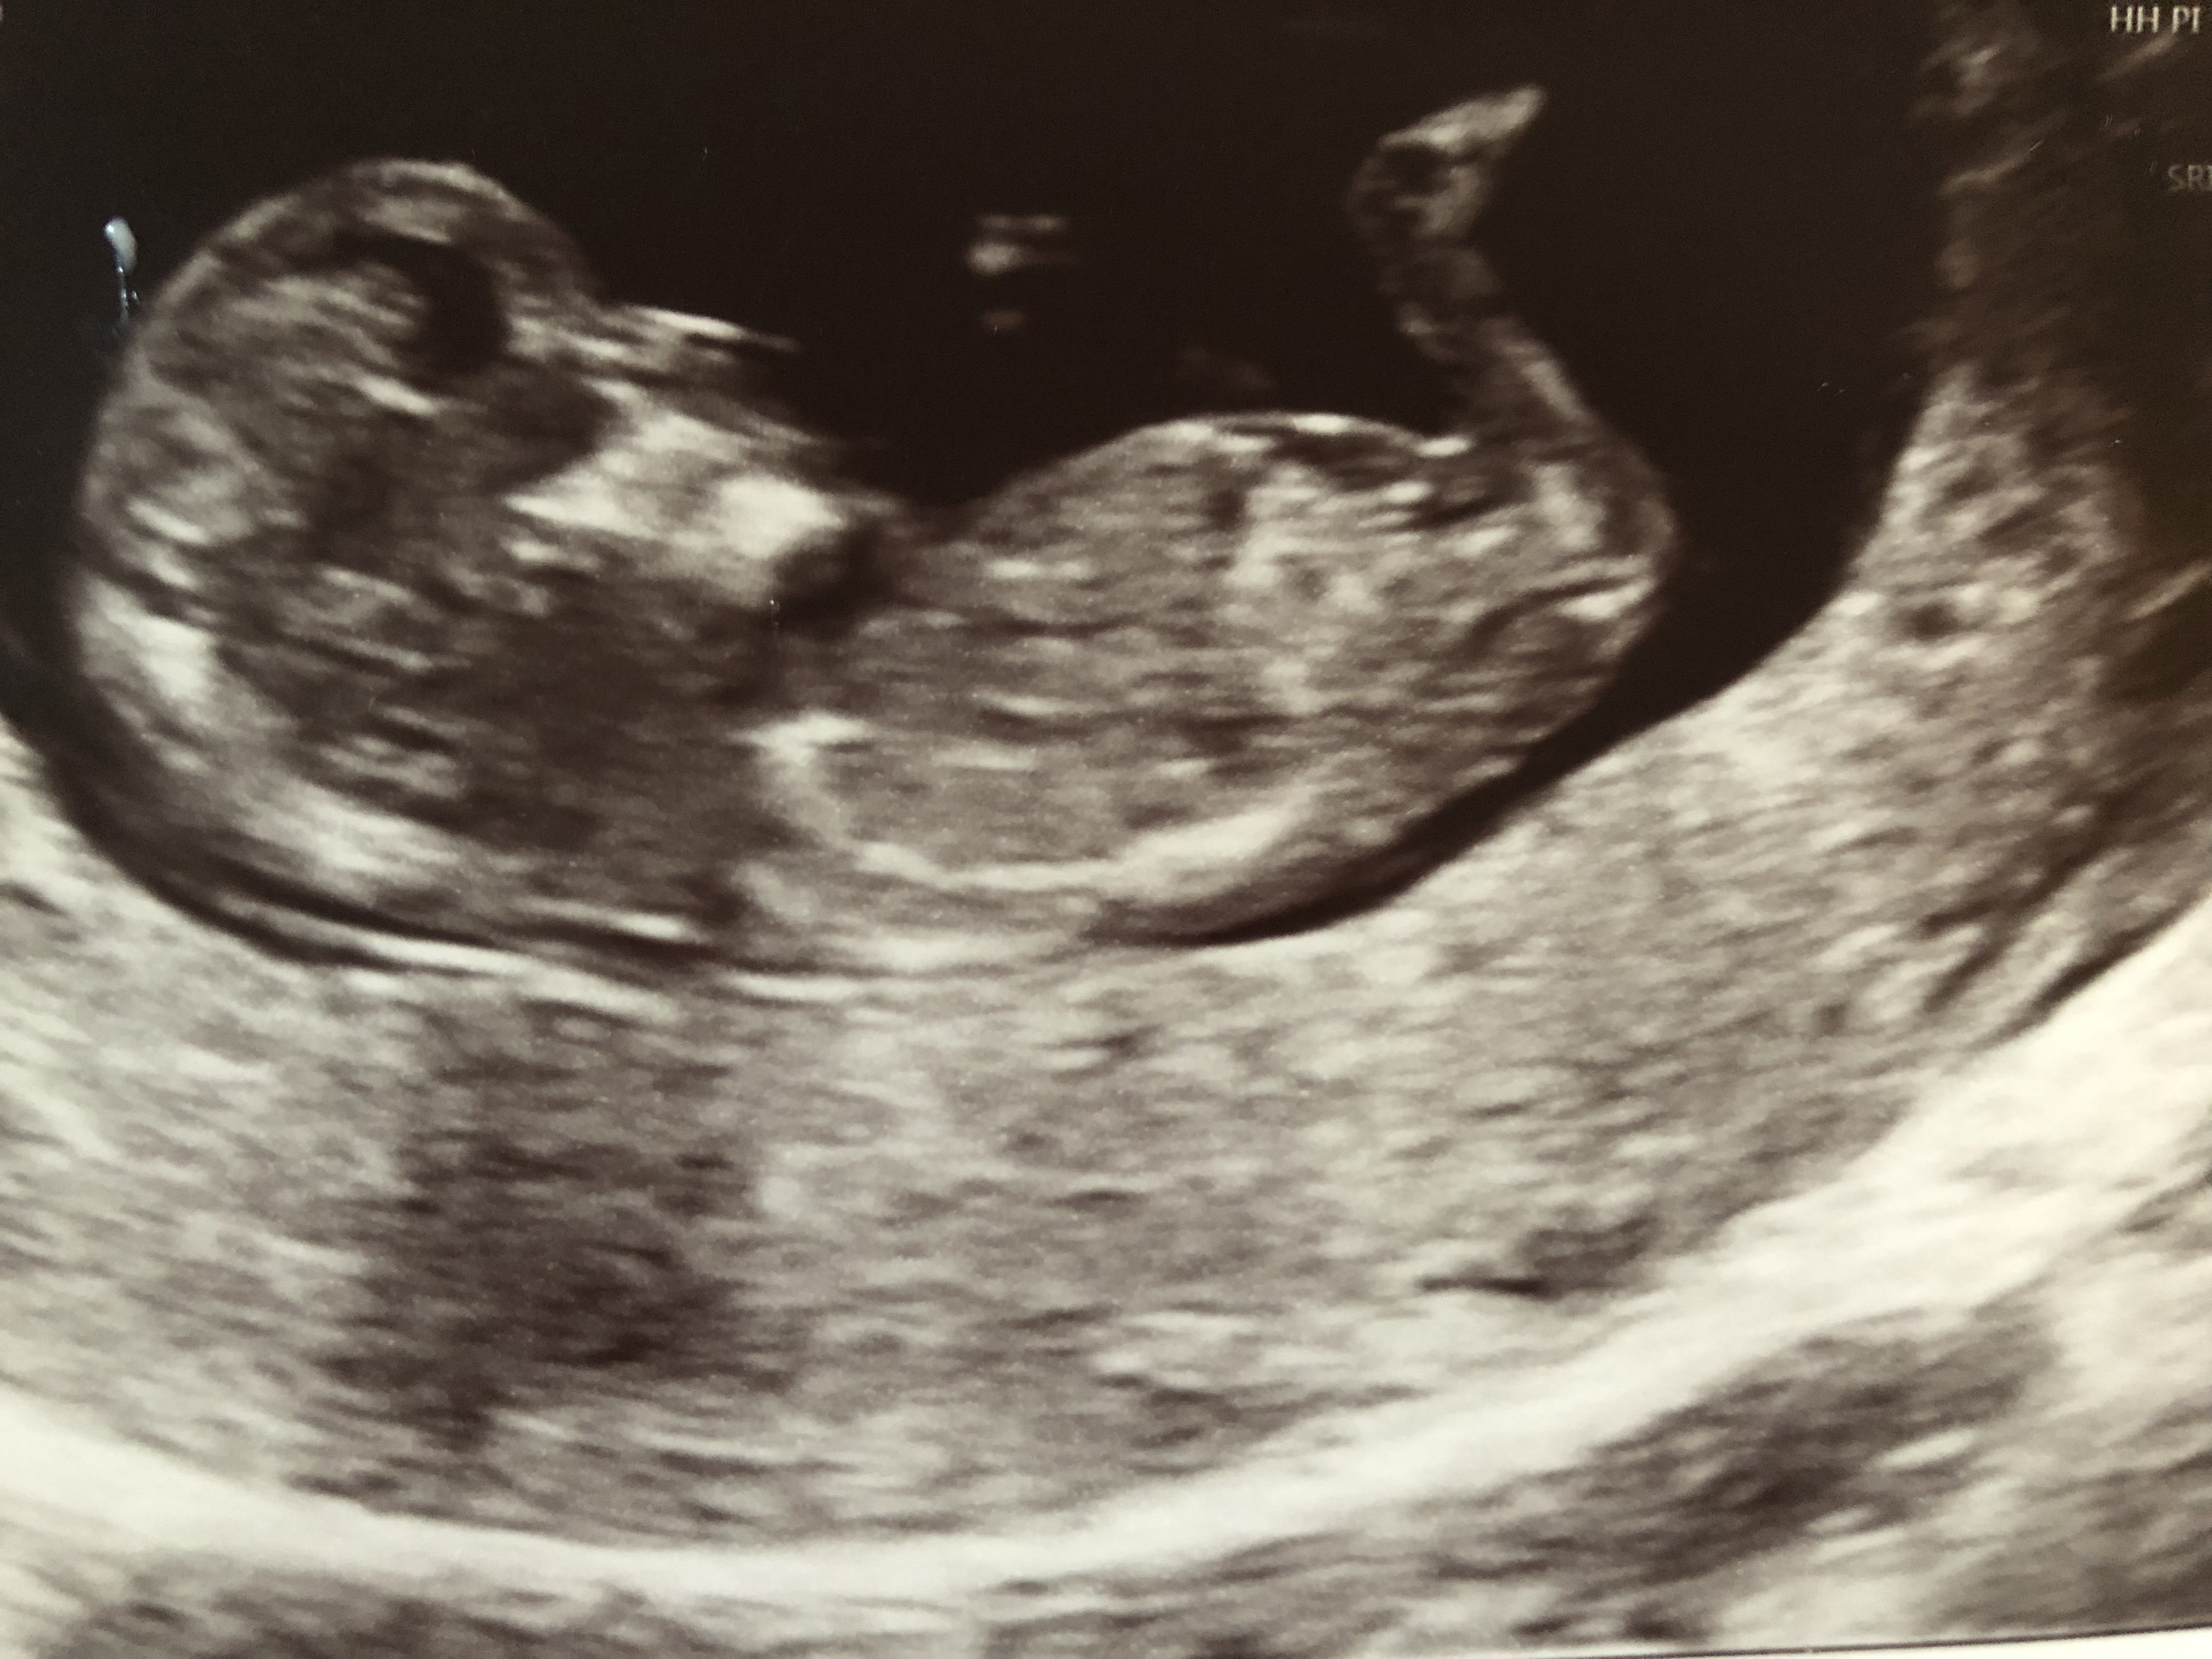

Have also included my 16 week scan pic just in case! Attachment 41945Attachment 41946Attachment 41947

This is difficult. I thought it was a girl based on first and second shot (but hard to see if it is the nub).

Then I looked at the last pic again. I leant towards boy then.